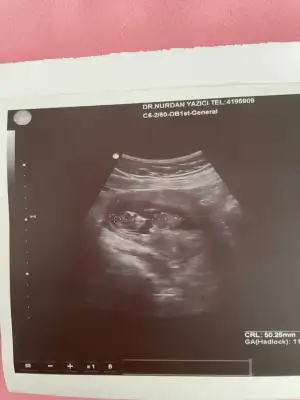

Merhaba. Bu ultrasonların yönünü algılama konusunda sorun yaşıyorum kafam biraz karışıyor kamera işin içine girince yönü değişiyor aslında sanırım.Şimdi daha detaylı da araştırdım bunu aslında sizin bebek resimde solda ama aslında sağda duruyor. Yani Erkek. konuyu açan arkadaşa da yanlış söylemiş oluyorum bu durumda.Vajinal ultrason aynalı gösteriyor diyorlardı burda hep ama araştırınca karından ultrasonun aynalı gösterdiğini öğrendim. Rami Teorisine göre bebeğiniz Erkek.